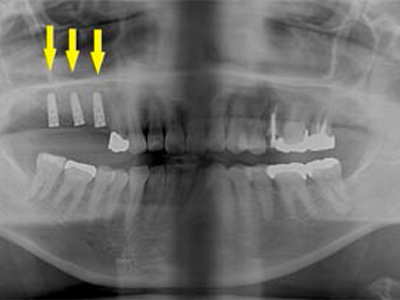

患者様は70代男性。写真は初診時の患者様のレントゲン写真です。

左右とも、上顎第一大臼歯を失っていました。

通常のレントゲン写真では骨量が十分かと思われましたが、CTを撮影してみると黄色の矢印部位、左側では少し骨の高さが足りませんでした。 -

CTを撮影して測定すると、右側はギリギリ10mmぐらいの高さで、左側は6mmほどしかありませんでした。